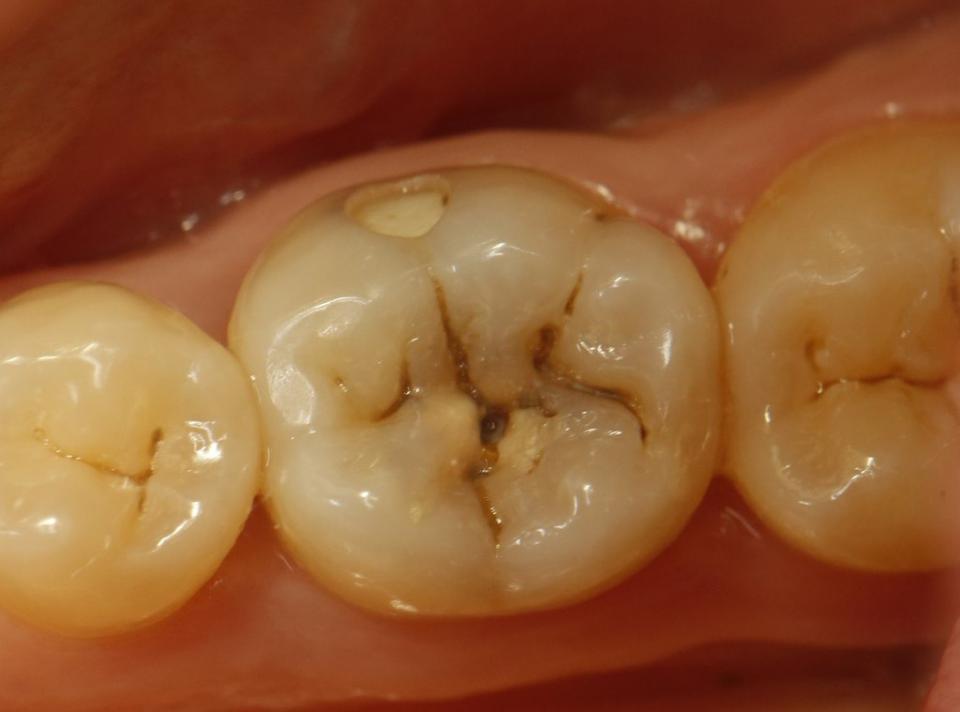

paraschyk1 Опубликовано 16 октября, 2015 Автор Опубликовано 16 октября, 2015 Это где ставят по 200гр?))бор нормальный стоит только гривен 40,а еще сам материал,полиры,паста полировочная,протравка,бонд, ершики для бонда,матрицца и матрицадержатель,анестетик,иголки доя карпульного шприца, ретракционная нить.Пачка перчаток 50 пар уже за 150гр перевалила,салфетки. А еще переодически новые наконечники надо покупать...Антисептики для рук и инструмента стоят дохера..А еще долгосрочные-амортизация ремонт установки, новые инструменты(пакеры,гладилки,зеркала...)А еще аренда(платный план) на который тоже идет свой материал(от 10 ки)... Вижу в теме. Ты забыл время. Время самое ценное. А пакеры и ершики копейки. Увы,но в Киеве еще можно поставить пломбы аля лепнина,за 200 грн. Но и срок им мал и вид соответствующий Но вот такую работу делать за 200грн я не буду,ну разве корешу.

paraschyk1 Опубликовано 16 октября, 2015 Автор Опубликовано 16 октября, 2015 Выпал недавно реставрированный жевательный семерка вместе со штифтами. Т.е. там остались одни корни, над десной ничего от зуба нет. Было 2 штифта, реставрация + обычная простая коронка сверху. Все это аккуратно выпало. Один стоматолог говорит, что даже браться не будет, мол через годик снова отвалится, только вырывать. Другой говорит, что здоровый корень, какой нафиг рвать, только делать. Ниже вариант спасения зуба,когда полная жопа. Такой зуб может бегать пять лет и более.

paraschyk1 Опубликовано 13 декабря, 2015 Автор Опубликовано 13 декабря, 2015 Починил форумчанена после неудачного лечения.